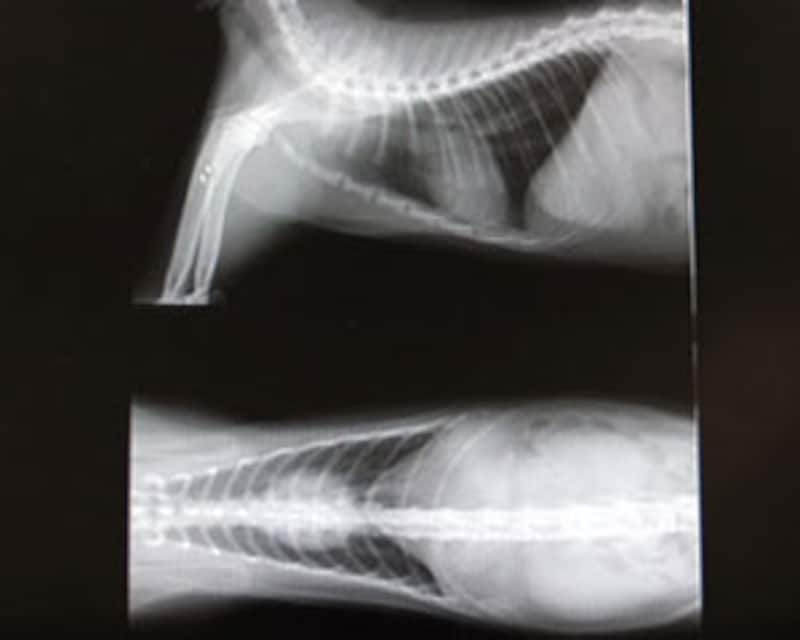

3.レントゲン検査

身体の前部分、後部分(胸部横臥と伏臥、腹部横臥と仰臥)臓器を撮影しました。